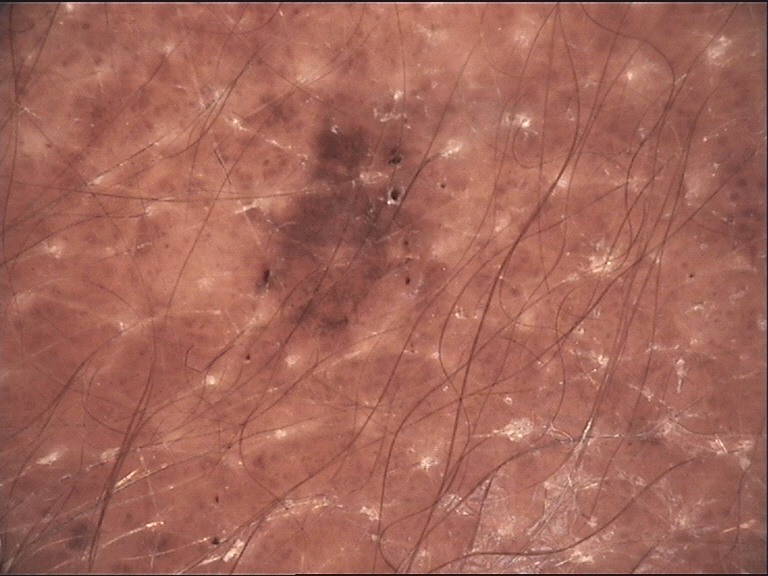

Melanocytic Nevus

| Atypical Network Irregular, broadened, broken network | Absent | Characteristic | Diff |

| Blue-White Veil Irregular blue-white structureless area | Absent | Variable | Diff |

| Regression Structures White scar-like or blue-gray peppering | Absent | Variable | Diff |